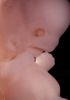

Carnegie Stage 19 (47 post-ovulatory days)

Most embryos at stage 19 are approximately 47-48 post-ovulatory days old and measure 17-20 mm in length. Distinguishing criteria for this stage include straightening of the trunk, the limbs extend nearly directly forward, toe rays are prominent, but interdigital notches have not yet appeared in the foot.